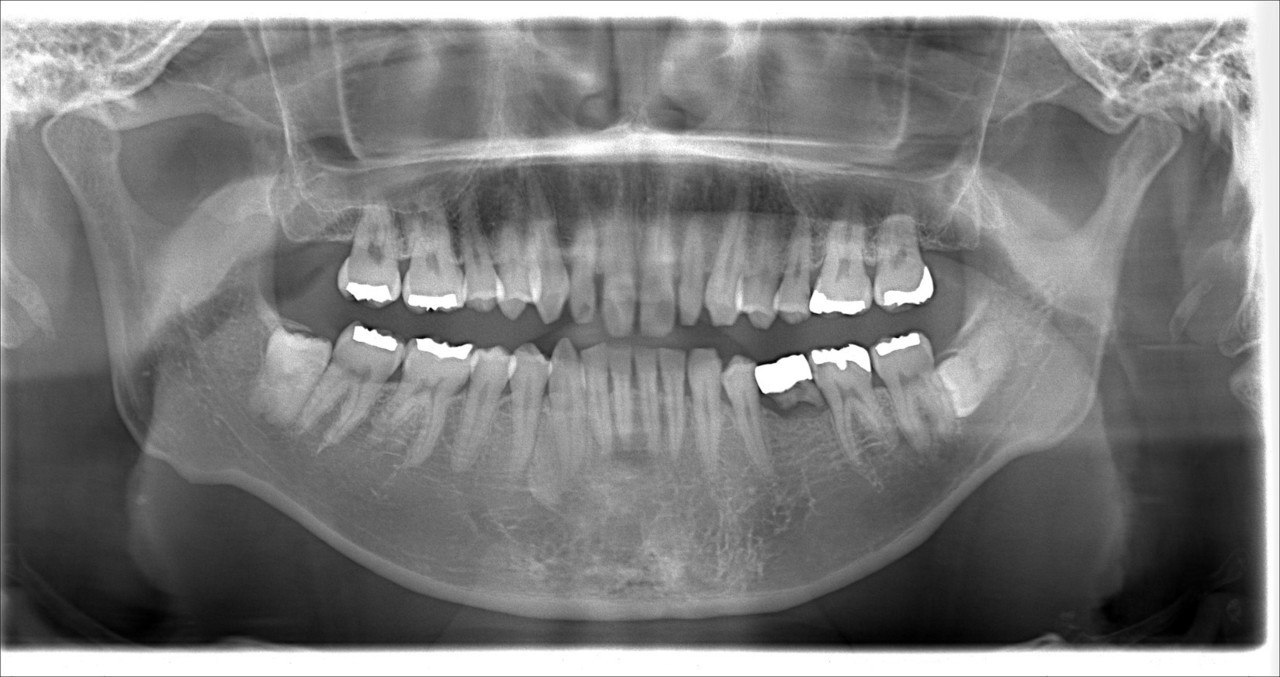

奥歯のインプラント症例③

治療前

治療後

治療内容

左側の奥歯3本の歯を失っており、かつ右側の奥歯のブリッジが破折していたため食べ物をうまく噛めないということでインプラント治療を行いました。

期間 4か月

費用 税込220万円

起こりうる副作用・リスク 保険外治療です。

手術後にインプラントの定期メンテナンスを怠ってしまうと、インプラント周囲炎になるリスクが高まります。